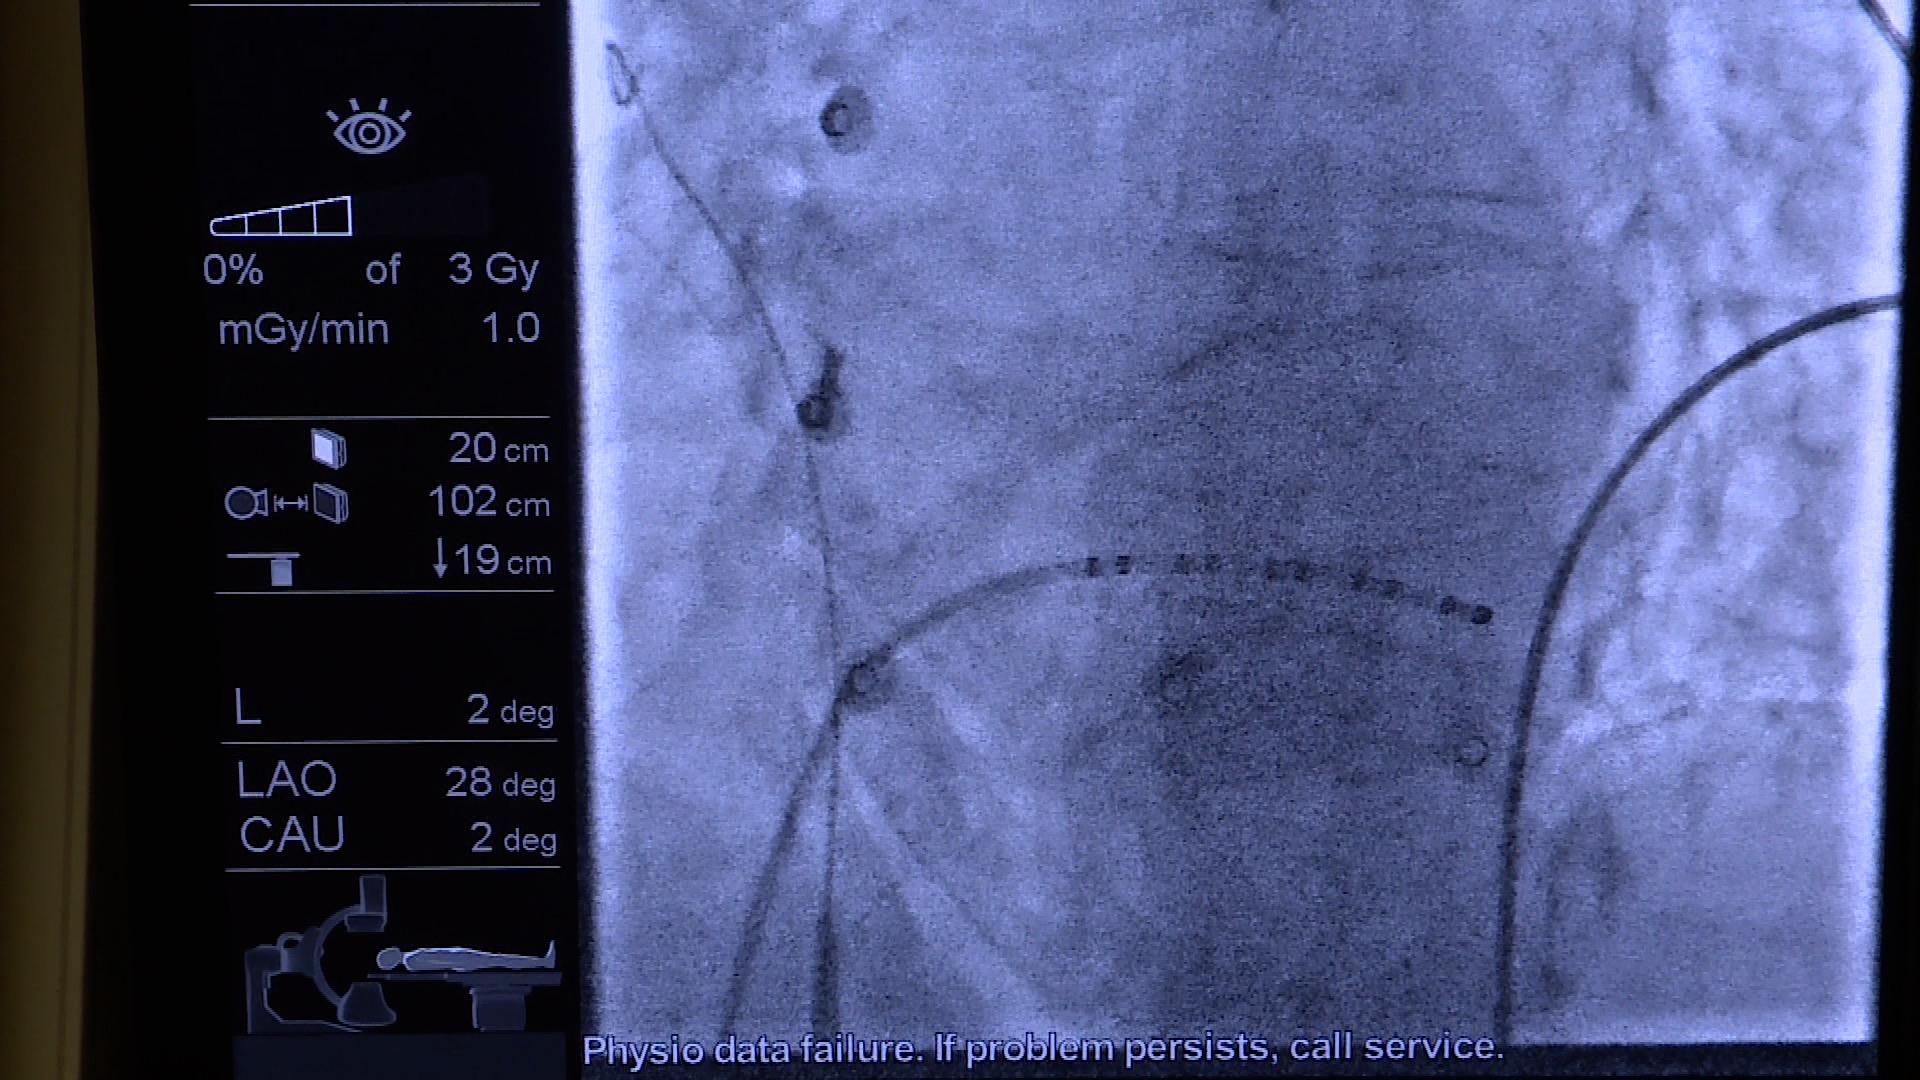

A korábbi eljárások úgynevezett termális energián alapultak, tehát égetéses, vagy fagyasztásos technológián, ez pedig nagyfeszűltségű mezőt hoz létre nagyon rövid ideig, és ezzel tulajdonképpen gyorsabb és sok szempontból biztonságosabb is a beavatkozás

– tájékoztatta a Zalaegerszegi Médiacentrumot Dr. Riba Ádám, a pacemaker és elektrofiziológiai laboratórium vezetője.

További előnye az újításnak, hogy a kezelésen átesetteknél kisebb eséllyel tér vissza a szabálytalan szívverés egy éven belül – fűzte hozzá Dr. Lupkovics Géza osztályvezető főorvos.